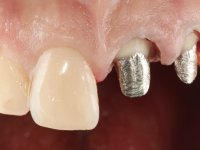

Foi feito o tratamento endodôntico dos dentes 2.1 e 2.2.de imediato, a sintomatologia que o paciente manifestava a isso impunha. Na mesma consulta foi realizada uma extensa gengivetomia com o bisturi elétrico, no sentido de expor os limites cervicais da fratura. Foram colocadas resinas compostas nos remanescentes radiculares com a intenção de reformular a emergência dos tecidos moles. Realizei a impressão dos remanescentes radiculares para confeção em laboratório de uma ponte provisória. A ponte provisória de 2 elementos, apresentava um formato que visava no futuro acomodar o coto dos espigões falsos cotos que iria ser cimentados nos remanescentes radiculares. Apresentava um reforço metálico palatino e dois apoios para os dentes adjacentes, um mesial e outro distal. Os remanescentes radiculares foram preparados para a confeção de dois espigões falso coto fundidos. As linhas de acabamento cervical foram definidas e os canais radiculares desobturados e preparados. A impressão foi realizada com a utilização de tutores de plástico com a técnica de dupla mistura. O afastamento gengival foi feito utilizando pasta de caolino. A ponte provisória foi rebasada em boca com acrílico auto polimerizavel, cimentada provisoriamente sobre as raízes e os apoios colados aos dentes adjacentes. No laboratório foram confecionados os E.F.C. fundidos, tendo o cuidado de preservar espaço para a definição no re preparo dentário da linha de acabamento cervical. Removida a ponte provisória foi feita a cimentação dos E.F.C. fundidos com cimento de ionómero de vidro reforçado com resina. A ponte provisória teve que ser retocada para permitir a acomodação dos cotos e simultaneamente foi readaptada à redefinida linha de acabamento cervical. Durante 2 meses a ponte provisória acompanhou a estabilização periodontal das raízes traumatizadas e simultaneamente conseguiu a maturação da arquitetura gengival.